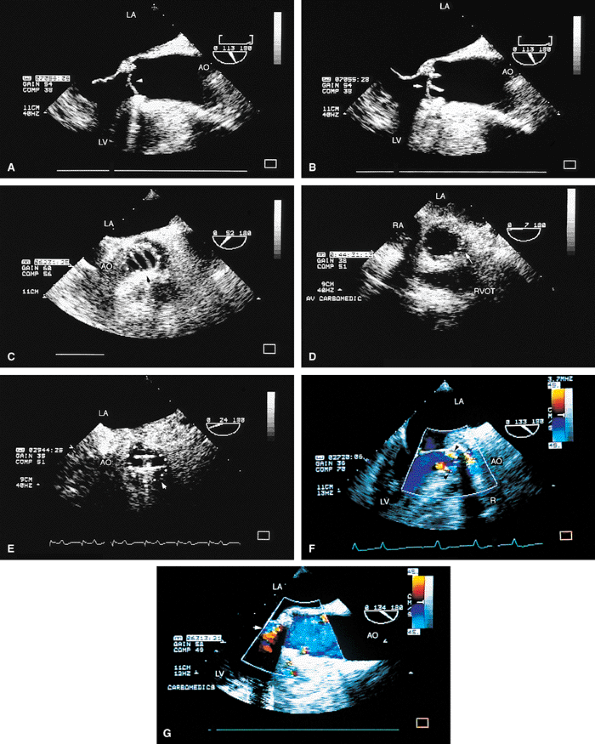

FIGURE 5.30. CarboMedics aortic prosthesis: normal. A. The prosthesis in the closed position in diastole (arrowhead). B. Both leaflets in the open position (arrow) in systole.C. The leaflets (arrowhead) are open in systole. The suture ring is also seen in C and in D and E (arrow). F,G. Two jets of normal mild aortic regurgitation (AR) (arrows) that are eccentrically located. LA, left atrium; AO, aorta; LV, left ventricle; RVOT, right ventricular outflow tract. |

FIGURE 5.31. CarboMedics aortic prosthesis: paravalvular regurgitation. A,B. The aortic regurgitation (AR) jet occupies essentially the entire left ventricular outflow tract (LVOT) proximally, indicative of severe regurgitation. In both A and B, the most proximal portion of the AR jet is not imaged because of acoustic shadowing (S) caused by the metallic prosthesis (P), calcification, or both. AO, aorta; RPA, right pulmonary artery; RVO, right ventricular outflow tract. |